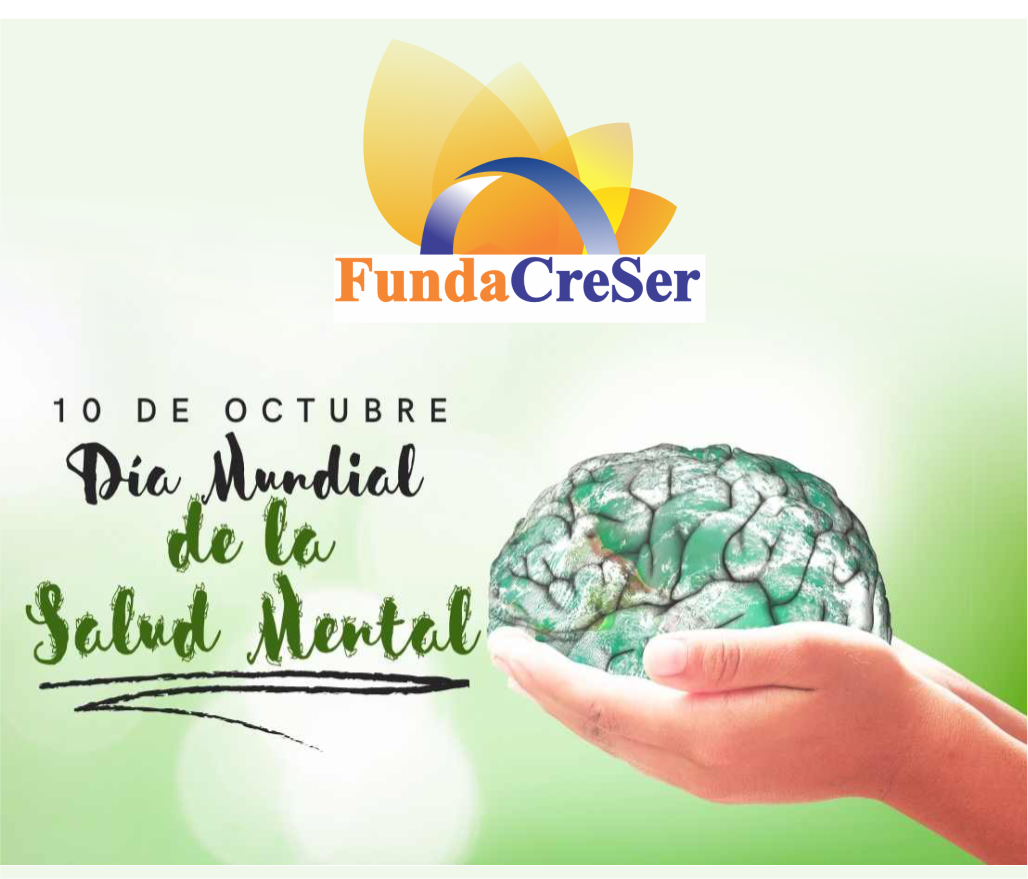

🧠 Efectos en la salud mental

Dependencia: La drogadicción puede llevar a la dependencia física y psicológica de la sustancia.

Ansiedad y depresión: La drogadicción puede aumentar el riesgo de ansiedad y depresión.

Problemas de memoria y concentración: La drogadicción puede afectar la memoria y la concentración.

Cambios en la personalidad: La drogadicción puede llevar a cambios en la personalidad y el comportamiento.